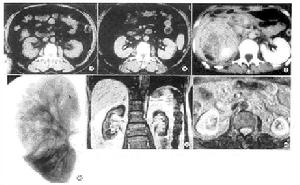

其它輔助檢查: 1.X線檢查 對慢性或久治不愈者,視需要分別可做尿路平片靜脈腎盂造影逆行腎盂造影排尿時膀胱輸尿管造影以檢查有無梗阻結石輸尿管狹窄或受壓腎下垂泌尿系先天性畸形以及膀胱輸尿管反流現象等此外,還可了解腎盂腎盞形態及功能,藉以與腎結核腎腫瘤鑑別慢性腎盂腎炎的腎盂呈輕度擴張或杵狀並可有瘢痕性畸形。腎功能不全時需用2倍或3倍劑量碘造影劑作靜脈快速滴入,此項檢查可能加重腎功能進一步惡化請注意並多次攝片才能使造影得到滿意效果腎血管造影可顯示慢性腎盂腎炎的小血管有不同程度的扭曲。必要時可作腎CT掃描或核磁共振掃描,以排除其他腎臟疾患